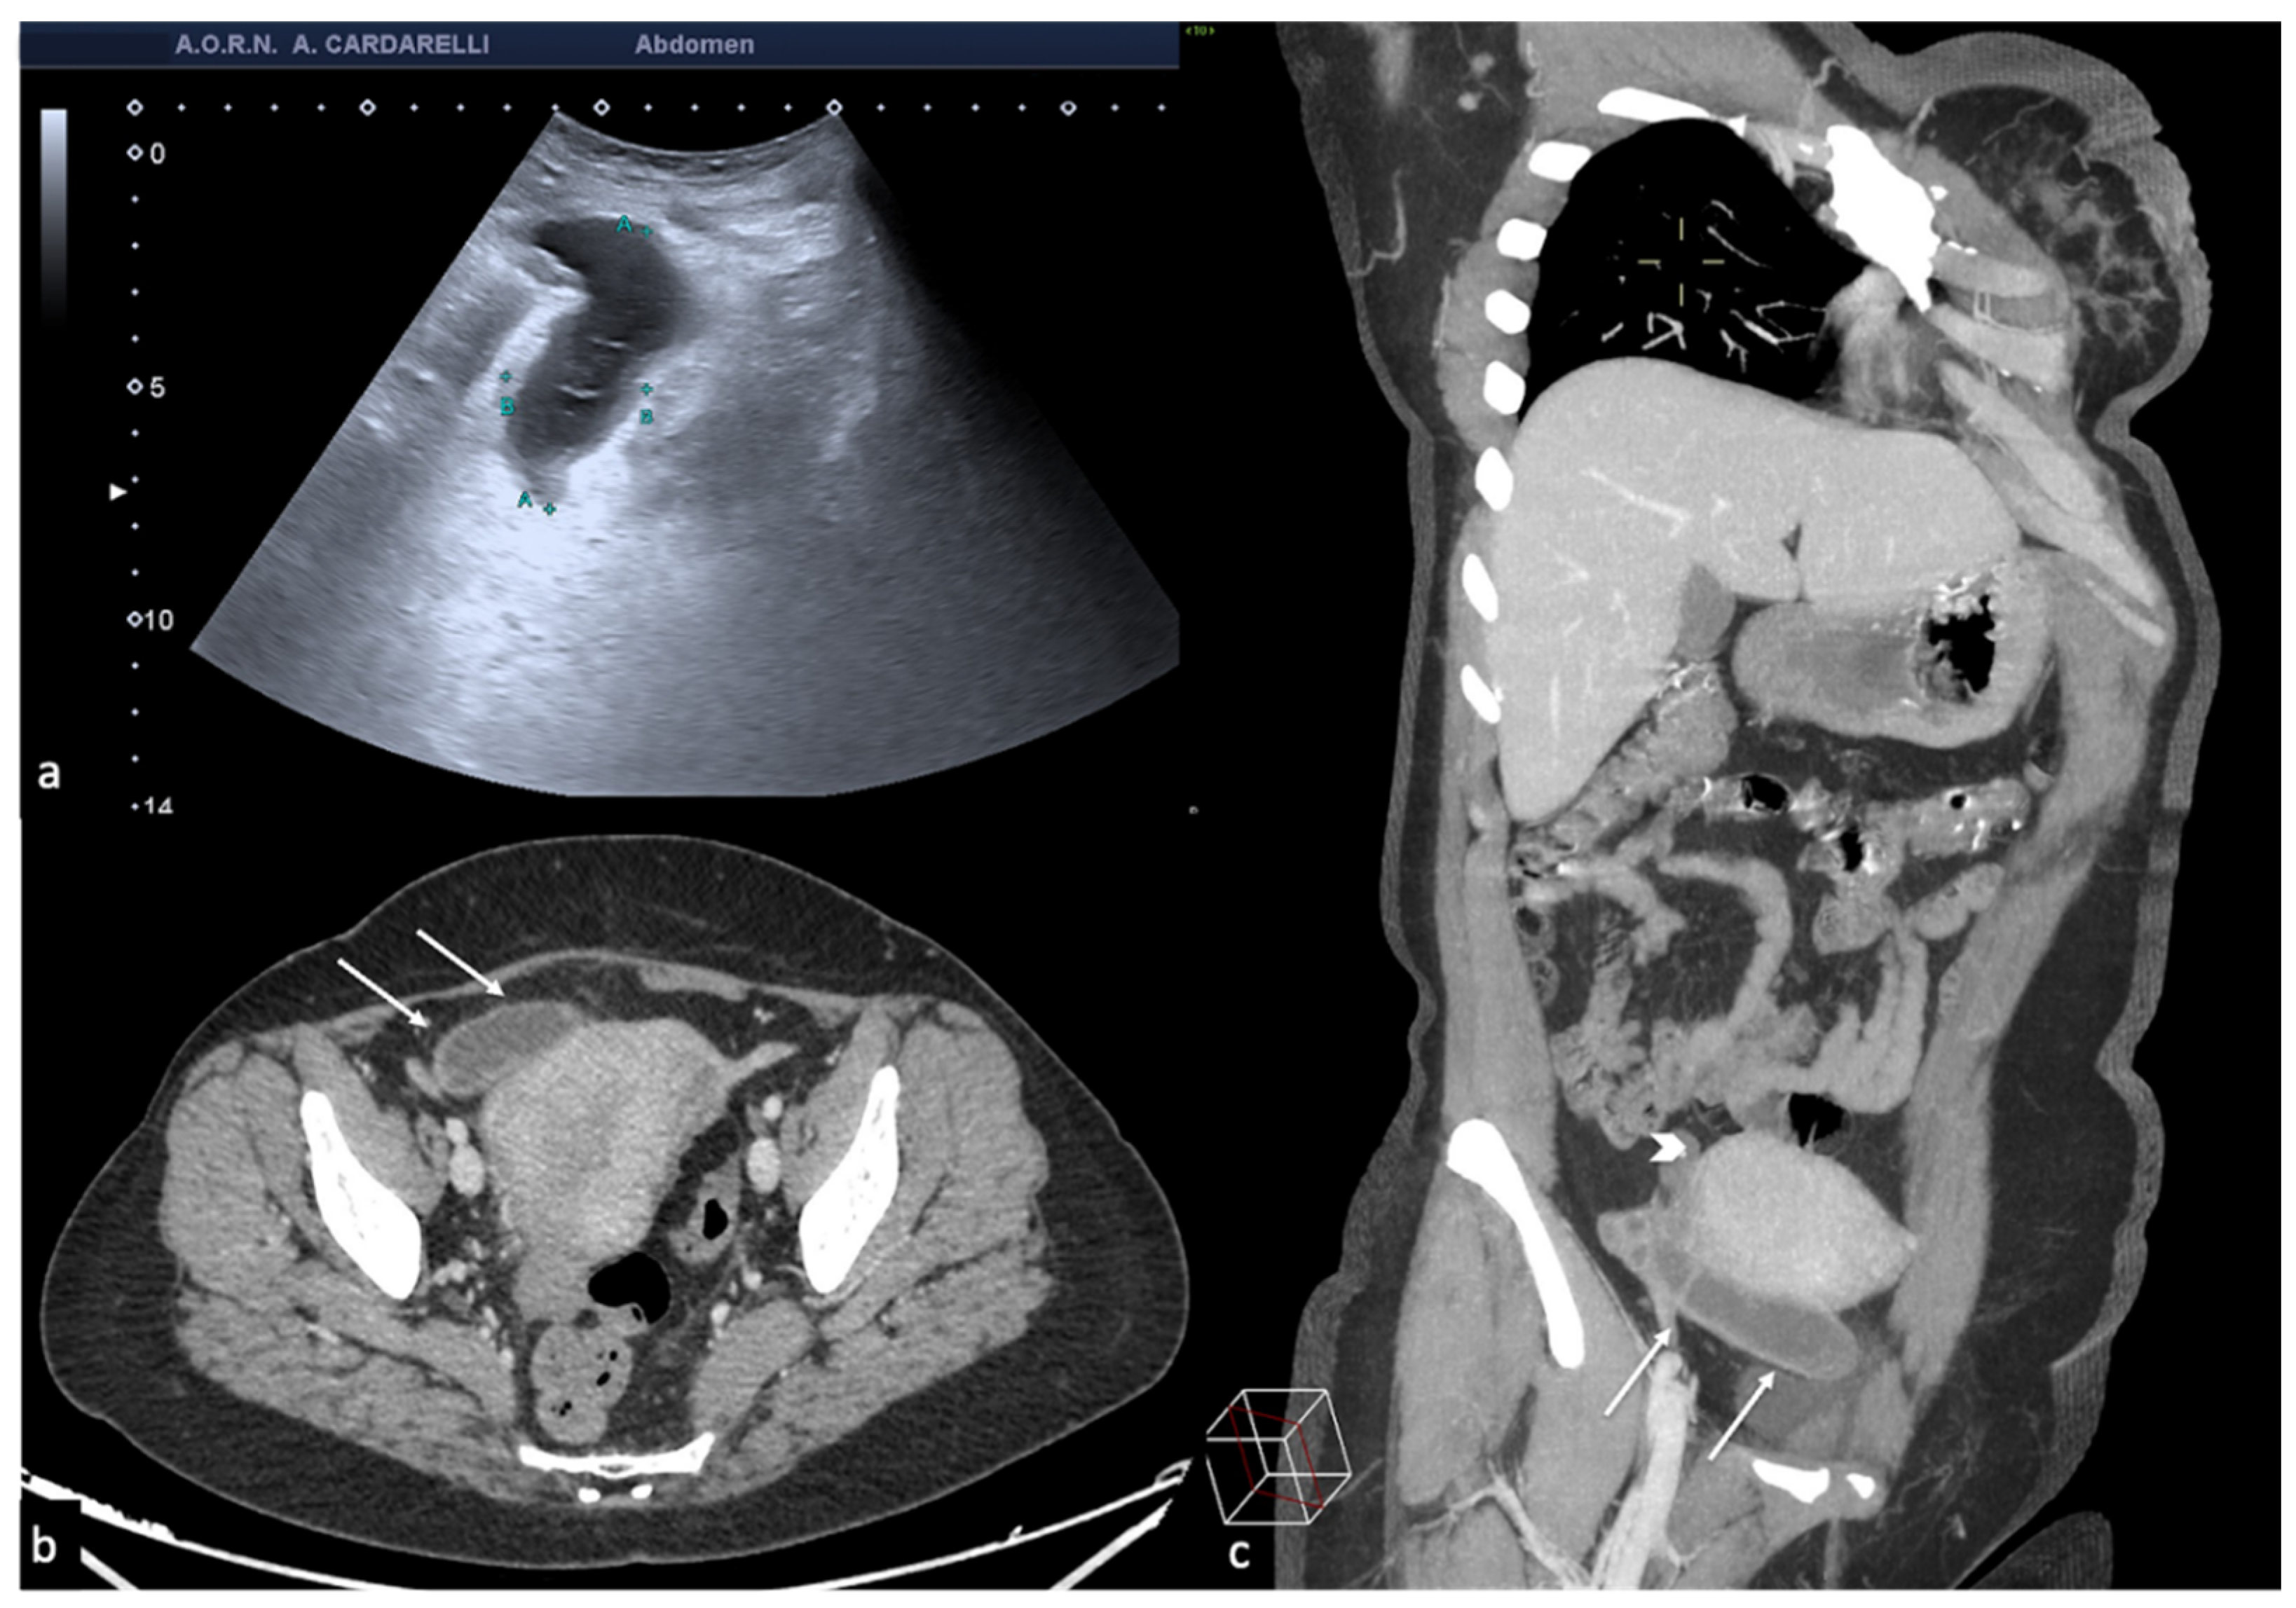

Figure 5. Pelvic inflammatory disease. US scan of the right adnexa (a) shows an anechoic oblong structure ((a), caliper). Contrast-enhanced axial CT image (b) and maximum intensity projection (MIP) coronal-oblique reconstruction (c) show tortuous and tubular fluid filled structure seen in the right adnexa ((b,c) arrows).